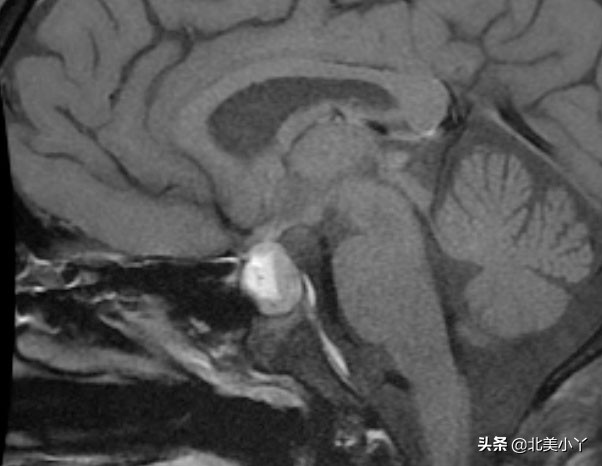

- 神经影像学检查,包括脑CT、垂体加强MRI。

- 神经影像学检查可以帮助诊断疑似的邂逅瘤,但是不能确诊邂逅瘤,确诊只能通过病理组织学分析。